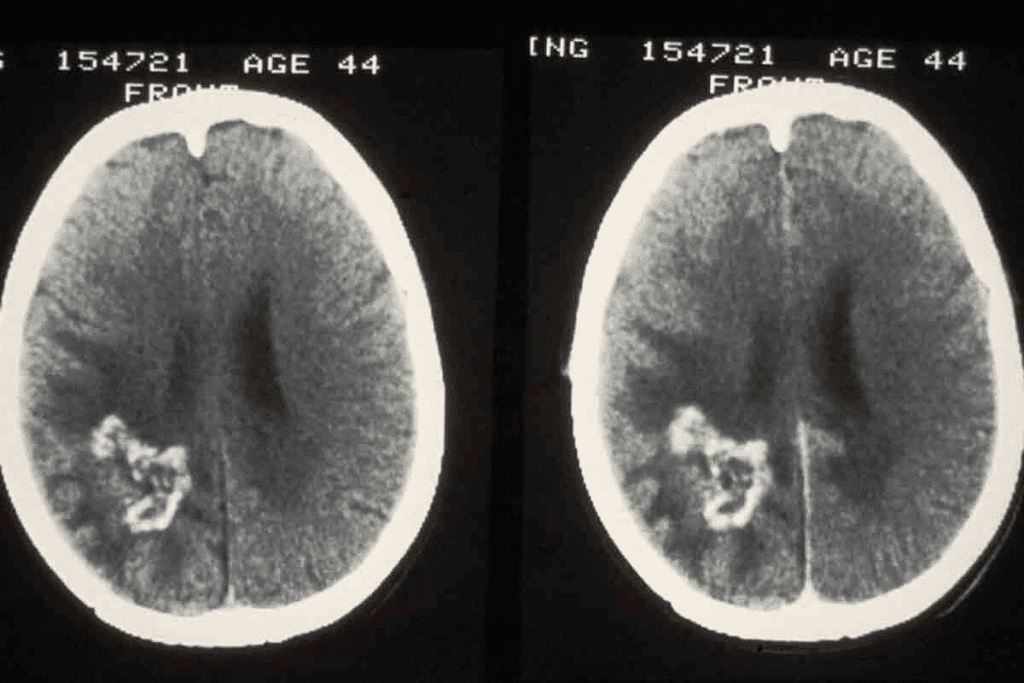

Malignant Brain Tumor MRI: General Characteristics

MRI is key in spotting malignant brain tumors by showing specific traits. When we look at MRI scans, we see certain signs that help tell them apart from benign tumors.

Common Features of Malignant Lesions

Malignant brain tumors show certain signs on MRI that indicate they are aggressive. These include irregular margins, heterogeneous enhancement, and necrosis. Irregular margins mean the tumor is growing into the brain. Heterogeneous enhancement shows different blood flow and activity levels.

Necrosis, or dead cells in the tumor, is a sign of malignancy. It looks like dark spots on T1 images and bright spots on T2 images. These spots are often surrounded by uneven enhancement.

“The presence of necrosis within a brain tumor is a strong indicator of malignancy, as it reflects the tumor’s rapid growth outpacing its blood supply.”

Key MRI Sign #3-4: Necrosis and Surrounding Edema

MRI scans are key in spotting brain tumors by showing signs like necrosis and edema. These signs help doctors diagnose and understand brain cancer better.

Central Necrosis as a Malignancy Indicator

Central necrosis in brain tumors shows they are cancerous. It happens when the tumor grows too fast and can’t get enough blood. This leads to cell death in the tumor’s center.

On MRI, necrosis looks like a dark spot in the tumor. It shows the tumor is aggressive.

The necrotic areas look different on MRI because of dead cells and blood. This makes the tumor look uneven.